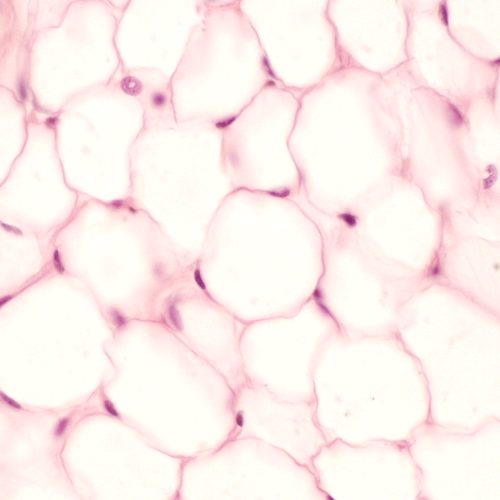

• White adipose tissue

• Normal body fat

• Very large spherical cells which may become polyhedral due to deformation

• Contain single fat droplet with cytoplasm reduced to thin rim net to plasma membrane

• Nucleus displayed to one side of cell and flattened by accumulated fat

• Routine histological techniques extract the fat, leaving a large unstained space

• Adipose tissue may be portioned by connective tissue septa visible to the naked eye